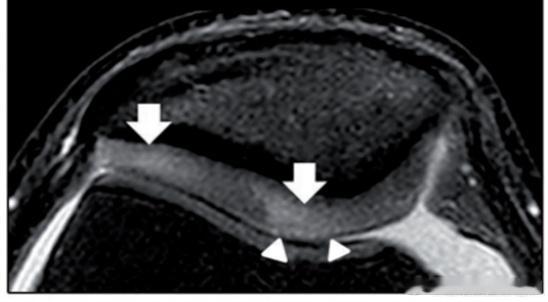

0级(图1):MRI显示软骨信号均匀。

——通常无症状

一级(图2):MRI显示软骨内信号变化,关节面完整

——可能不会引起疼痛